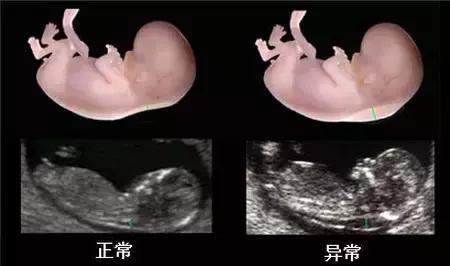

简单来说,它是通过B超手段测量胎儿颈项部皮下无回声透明层较厚的部位,用于评估胎儿是否有可能患有唐氏综合征的一种方法。

据南京世纪现代妇产医院产科医生介绍:一般来说,NT值<2.5mm时判断为正常,而当胎儿NT值(颈项透明层)大于或等于2.5毫米时,可判断为颈项透明层增厚。

颈项透明层增厚越明显,表示胎儿异常机会就越高,异常程度也越严重。总得来说,如果NT值偏高,那么胎宝宝可能会存在: